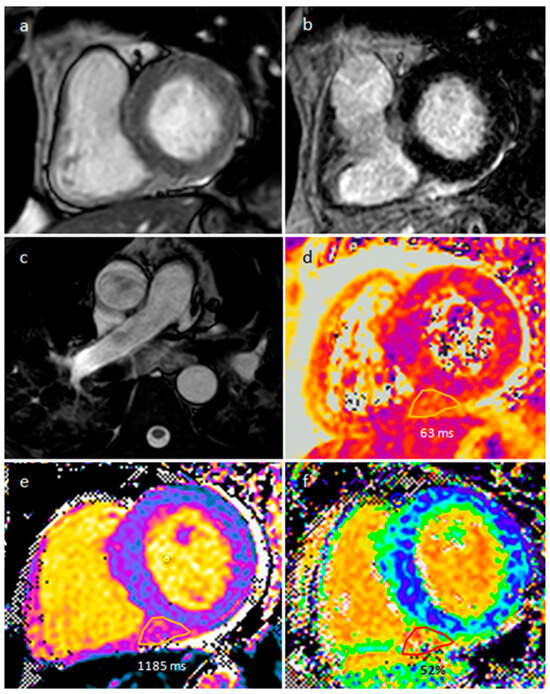

| Myxoma | Adulthood. Carney complex. | LA | Usually, asymptomatic. Rarely, intracardiac obstruction, embolic events and constitutional symptoms | Mobile mass arising from the IAS | Globular or spherical, with a friable surface and heterogeneous internal echogenicity | Heterogeneous, low attenuation, may be calcified | Isointense T1w, High T2w, heterogeneous LGE |